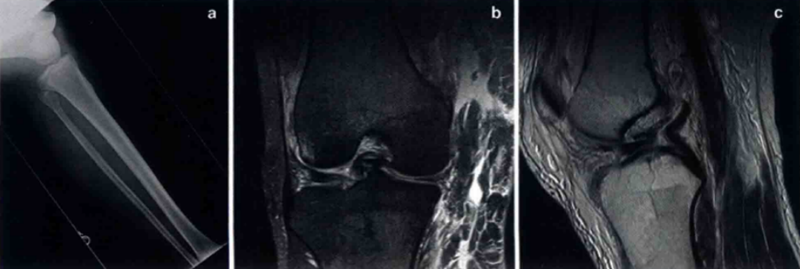

在全面体格检查后,应进行正、侧位X线检查证实,以诊断骨折和评估股骨、胫骨的移位。术后X线可用于评估复位后关节力线是否恢复。MRI在鉴定损伤结构、程度和部位上十分有用。在膝关节脱位和/或多发性创伤时使用CT血管造影术来确保血管无损伤。

图 a.膝关节脱位X线片;b.膝关节脱位的MRI冠状位;c.矢状位MRI